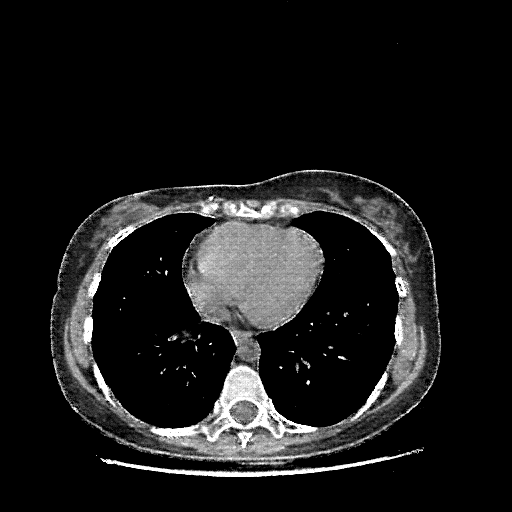

Generated VENOUS CT scan (A→B translation)

Full window (WL 1023.5, WW 4095 β†’ Low βˆ’1024, High +3071)